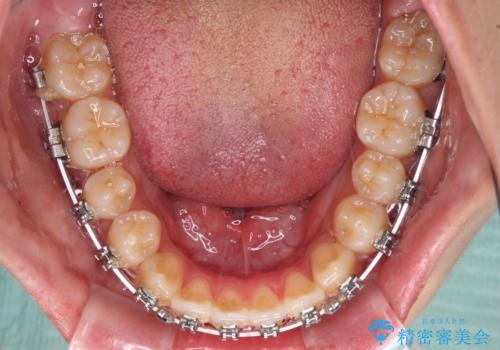

- メタルブラケット

- 前歯の開咬と、受け口による咬み合わせの悪さを気にして来院された患者様です。

上顎歯列が狭窄していたため、急速拡大装置により上顎骨を側方に拡大し、その後ワイヤー装置にて矯正治療を行うこととしました。

舌の突出癖が開咬の原因であったので、改善のための舌トレーニングを行っていただきました。

舌トレーニングは後戻りにも大きく影響するため、とても重要なトレーニングです。